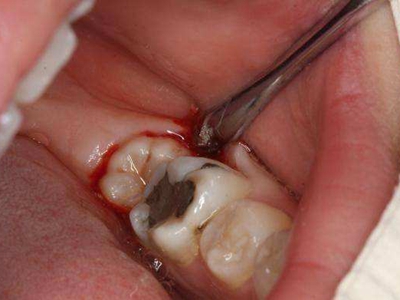

牙齿

缺损

智齿冠周炎大牙发黑缺了一半图

智齿冠周炎患者可出现第二磨牙龋坏变黑,是由于智齿倾斜阻生,与第二磨牙之间形成间隙,间隙不易清洁,食物和细菌积存,长此以往可导致牙齿龋坏发黑甚至出现缺损。